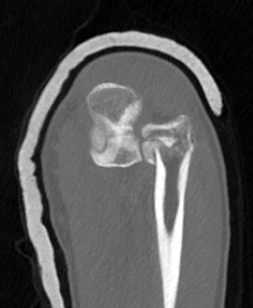

Monteggia variant

Definition

Elbow dislocation + olecranon fracture + radial head/neck fracture +/- coronoid fracture

Complex proximal ulna fracture with radial head replacement subluxation